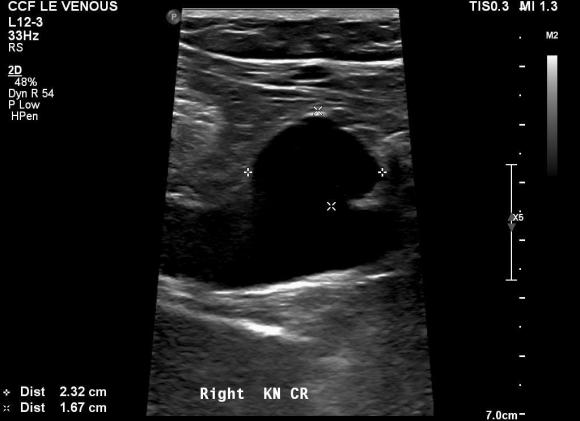

Patient is a middle aged man with history of DVT and PE who in preoperative workup for another operation was found to have a popliteal venous aneurysm affecting his right leg. Unlike the recently posted case (link) which was fusiform, this aneurysm was saccular (CT above, duplex below). Popliteal venous aneurysms have a high risk of pulmonary embolism because: they tend to form clot in areas of sluggish flow and once loaded with clot, will eject it when compressed during knee flexion.

preop-duplex